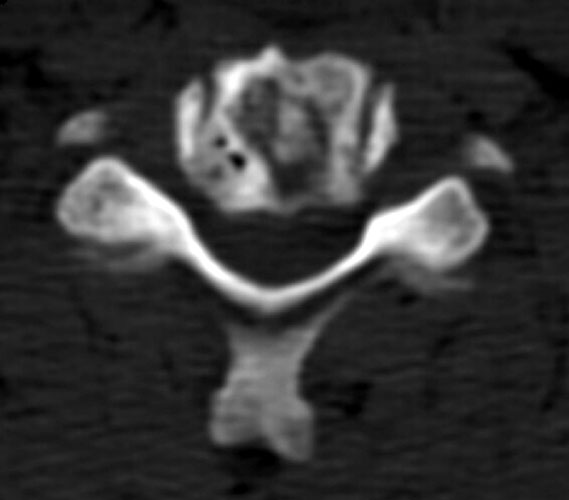

8 months later, the follow-up films demonstrate lucency at the graft site worrisome for resorption. Figure _. Axial CT examination, without contrast.

The axial images, and the sagittal reconstructions (not shown) show some central lucency in the region of graft placement, suggesting partial resorption of the graft material.